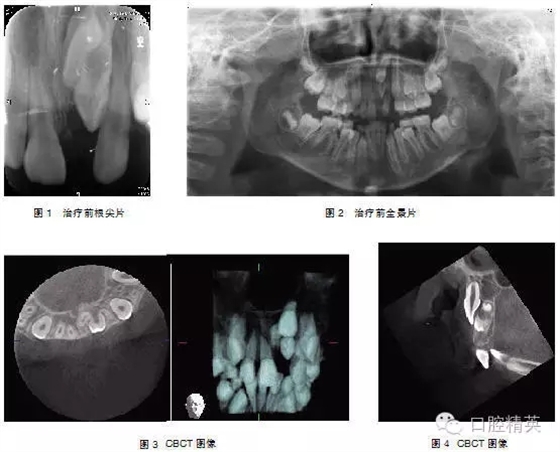

典型病例1: 患者,男,10歲,因左上前門牙未萌出于2009年10月來上海第九人民醫(yī)院預(yù)防、兒童口腔科就診。檢查: |1未萌,1| 全萌,1|2之間間隙為4mm。牙片及全景片示: |1骨內(nèi)埋伏,1| 2之間有埋伏多生牙,多生牙與 |1的重疊,不能清晰顯示多生牙和 |1在頜骨中的具體方位及相關(guān)關(guān)系(圖1-2),采用CBCT掃描后,圖像能清晰顯示多生牙和 |1的形態(tài)、大小、數(shù)目、牙根發(fā)育情況、在頜骨中具體位置、萌出方向及相互關(guān)系(圖3-4),經(jīng)手術(shù)證實情況與CBCT圖像顯示完全一致,手術(shù)拔除多生牙, |1作外科開窗術(shù)+正畸牽引治療。